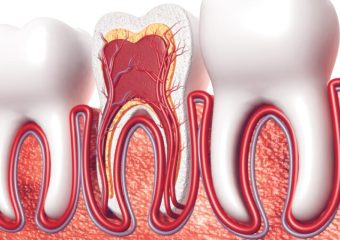

- عصب کشی دندان و درمان ریشه

درمان ریشه دندان یکی از روش های بسیار موثر برای نجات دندان بیمار است. این روش، برداشتن پالپ عفونی از کانال هایی را در بر می گیرد که در داخل ریشه دندان قرار داشته و پس از آن، دندانپزشک، کانال مورد نظر را به منظور جلوگیری از عفونت یا آسیب بیشتر مهر و موم می نماید.درمان ریشه دندان بسته به ناحیه تحت درمان در دهان و پیچیدگی شرایط ممکن است یک یا چند جلسه به طول انجامد. پس از اتمام درمان، دندان باید یا پر شود و یا با روکش ترمیم گردد تا عملکرد و زیبایی آن نیز احیا شود. زمان بهبودی نیز متفاوت است اما به طور معمول، هر نوع ناراحتی خفیف طی چندین روز برطرف خواهد شد.

با درمان ریشه، باکتری هایی که باعث عفونت شده اند از بین خواهند رفت. این مسئله از گسترش عفونت به سایر نواحی دهان مانند استخوان فک، بافت های نرم و فضاهای صورت جلوگیری می کند. پس از برداشتن پالپ عفونی، کانال ریشه تمیز و ضدعفونی شده و از گسترش پوسیدگی دندان در مسیرهای آن جلوگیری می شود.